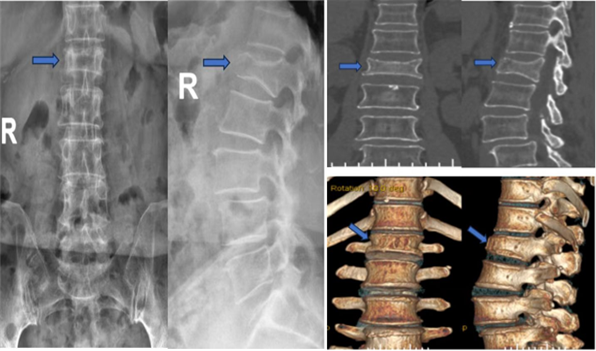

1、DR,CT,MRI均可用于骨质疏松性骨折的诊断,直观显示骨折区域。

DR CT